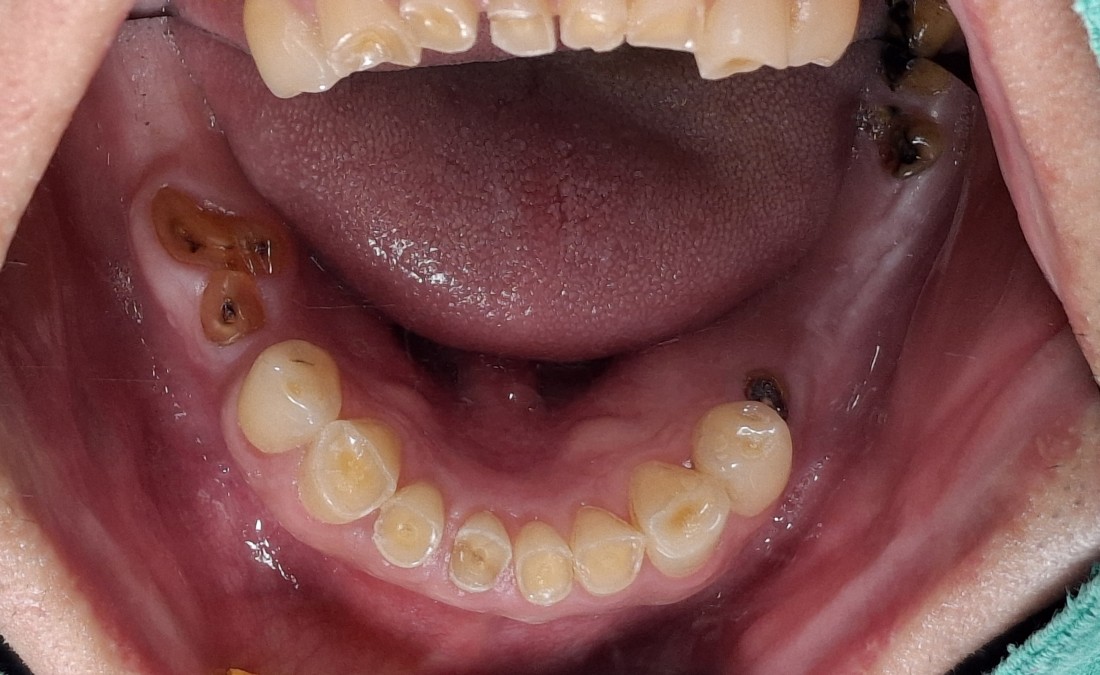

수완동 임플란트 치과에서는

임플란트 수술을 하기 전에

자연치아를 최대한 살려서

오래 사용하실 수 있도록

여러 진료를 추천해드리는데요.

그 중 하나인 잇몸치료는

보험이 적용되어

한 회당 2만원 대의 금액으로

2회 정도 수완동 치과에 내원하시면

잇몸염증을 해결하고

자연치아를 오래 사용할 수 있는

지름길이 되는 진료입니다.

수완동 임플란트 치과는

자연치아를 살릴 수 있는

최첨단 신경치료 기기를 도입하여

최소 통증의 치주치료가 가능합니다.

분과별 전문의 5인 대표원장의

협진 시스템으로

단 한 개의 치아라도 더 살리기 위해

최선을 다하고 있으며,

임플란트 수술이 필요한 경우에도

최소한의 개수만 식립하여

최대 효율을 얻을 수 있도록

진료시스템을 갖추고 있습니다.